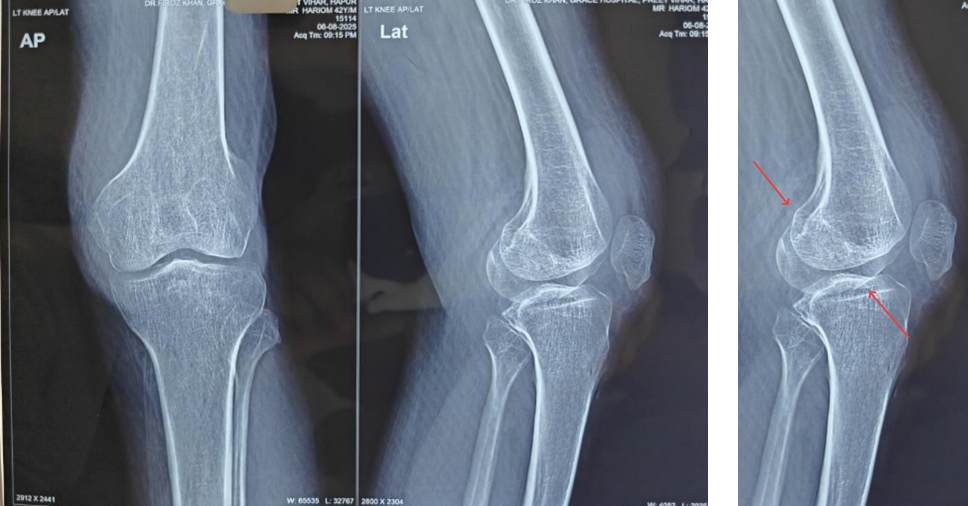

Radiographs (Fig. 1) and computed tomography scan (Fig. 2) of the knee revealed an undisplaced Hoffa fracture of the medial femoral condyle.

Figure 1: Pre-operative X-rays of the left knee showing an undisplaced medial femoral condyle Hoffa’s fracture.